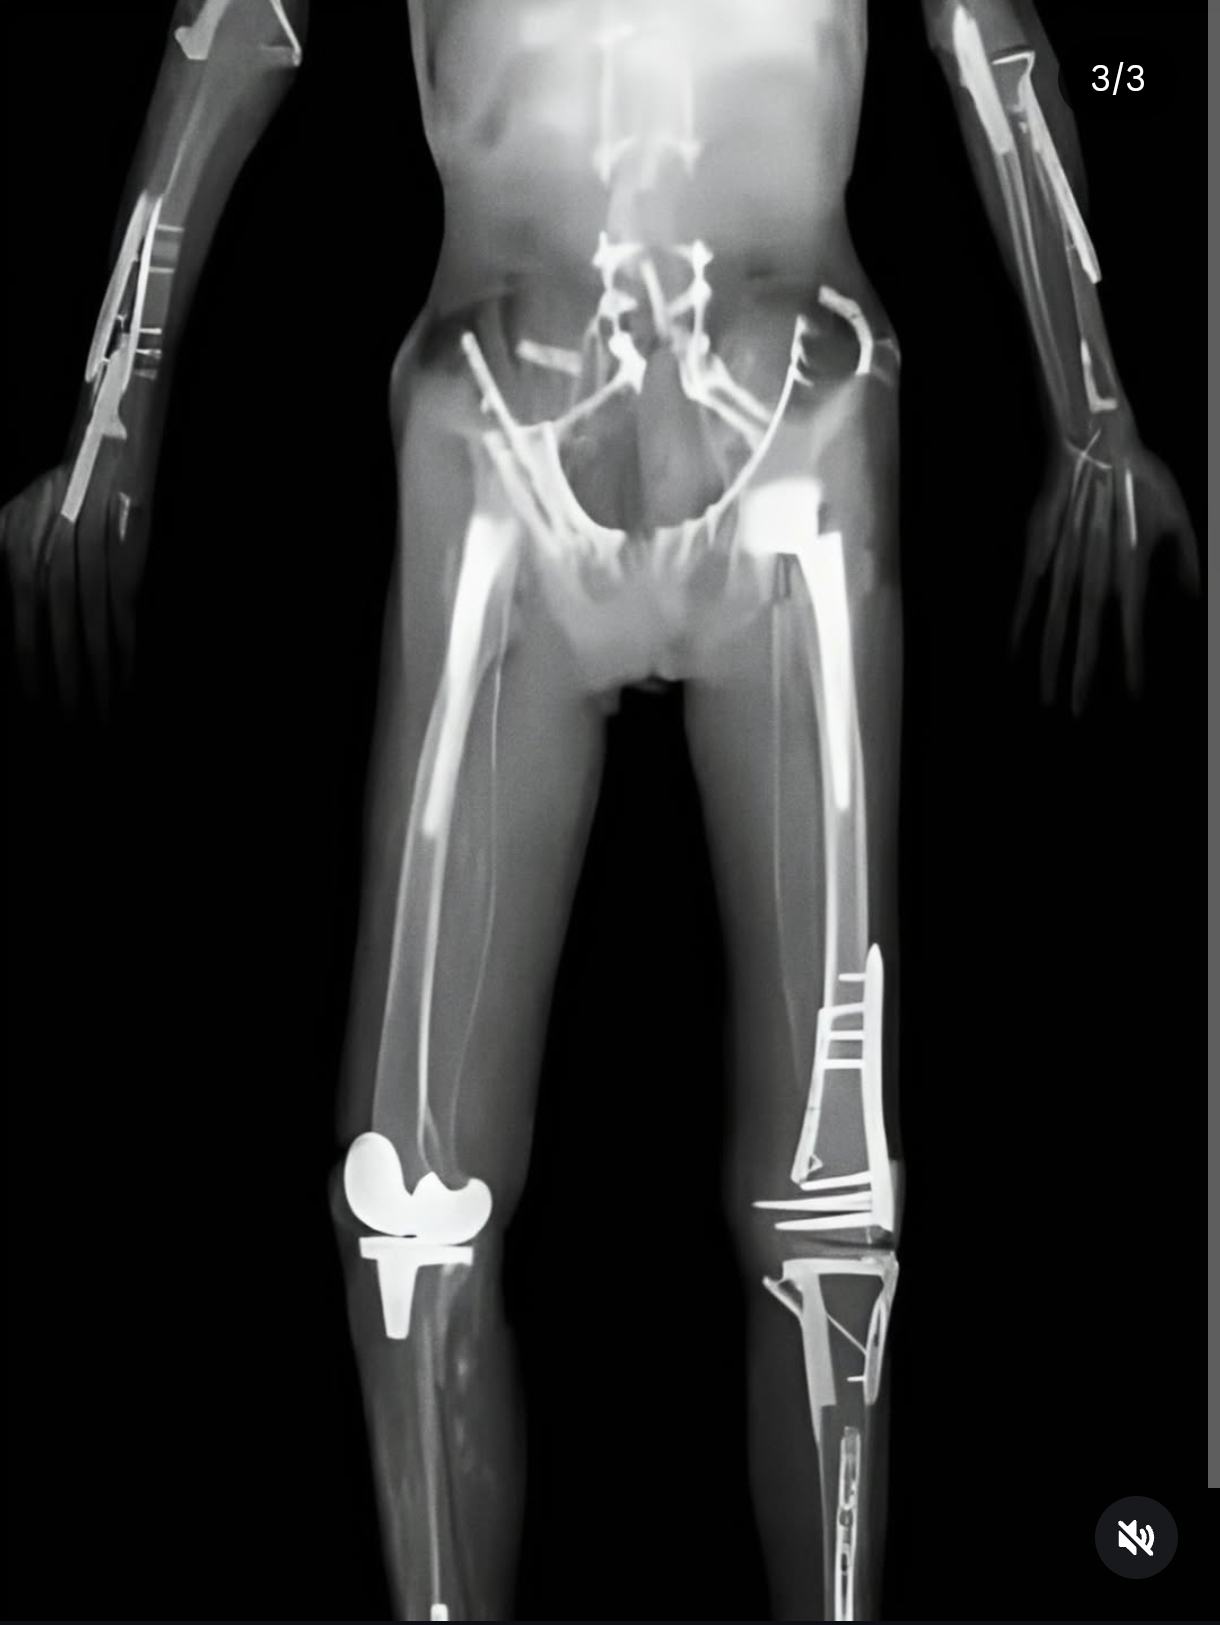

Travis Pastrana? Za zivot mel pres 30 operaci, pres 90 zlomenych kosti a vic jak 25 otresu mozku. Zakladatel Nitro circus, zavodnik v Motocrossu, Rallycrossu, Nascar, Rally, MTX Freestyle, zavodni cluny a pak v soukromi nejaky ty triky na kole

Když vidím takovýho kovu, nepotřebuje to přimazávat? Našroubovali mu někde maznice?

extrémní DH/Enduro na MTB? Takhle by mohl vypadat typan, co nedoletěl 30m přescesťák

u security na letisti ma asi dost zabavu